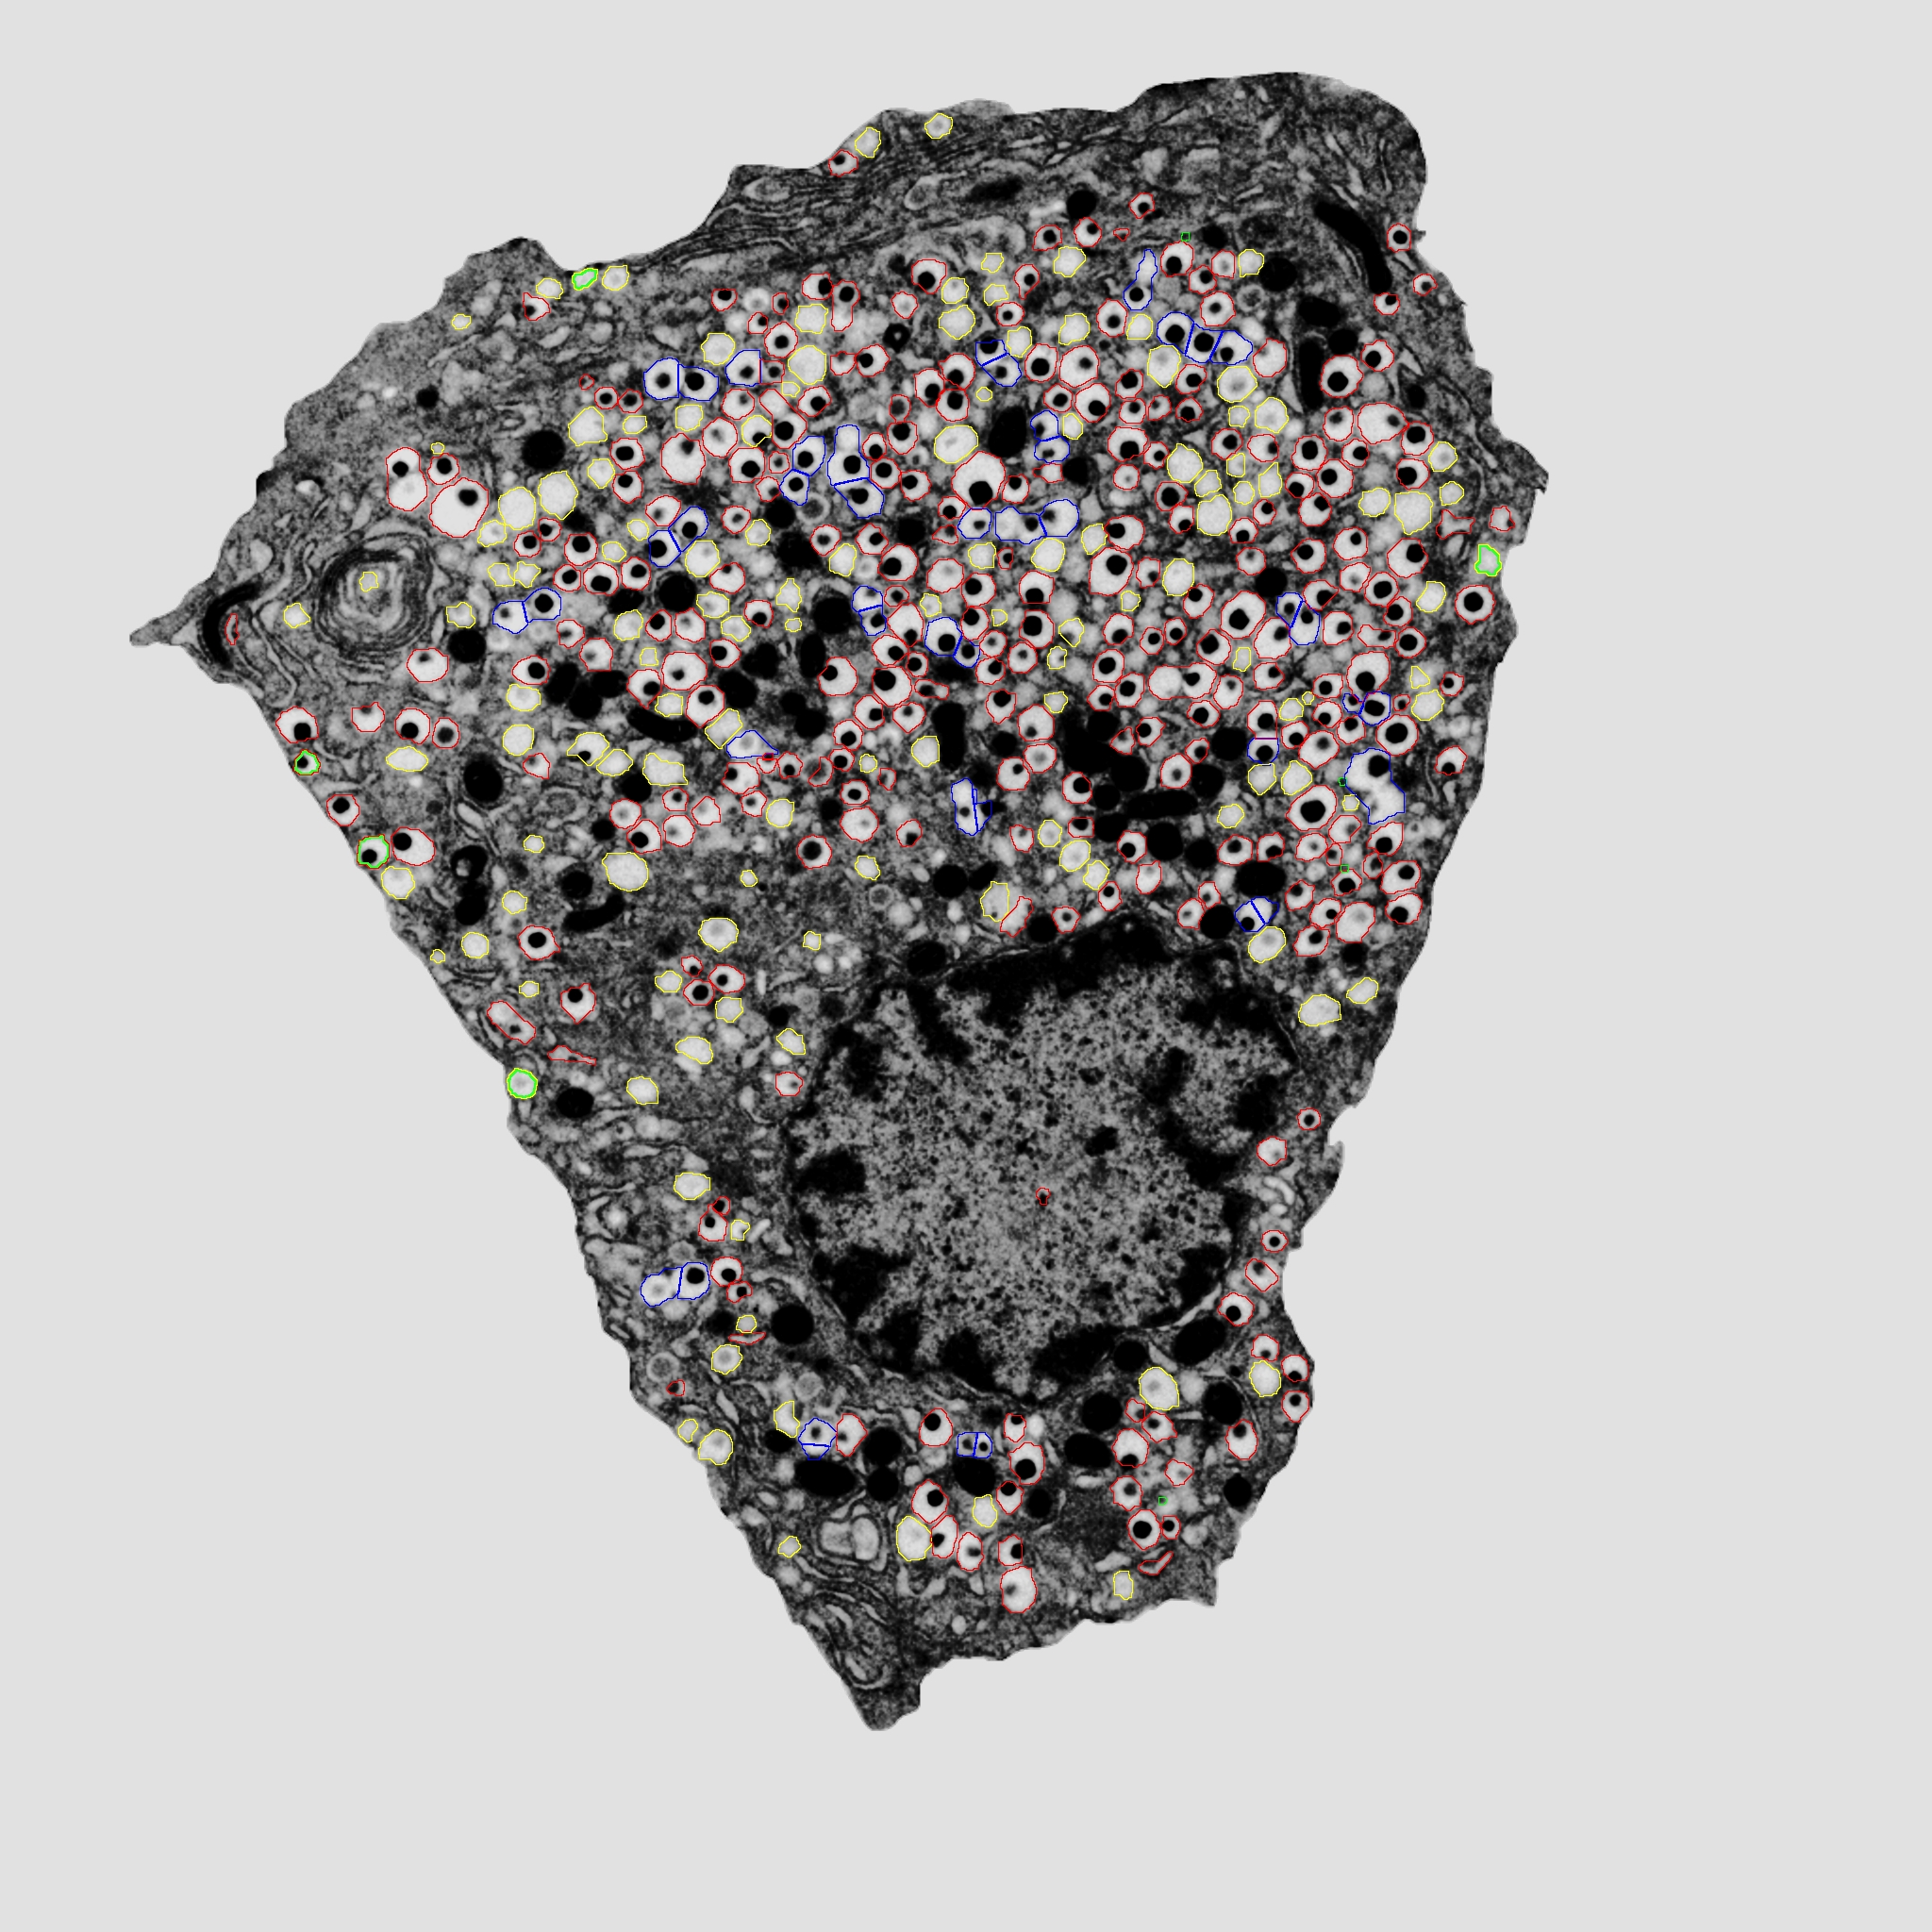

4. 이자 베타 세포의 인슐린 과립

이자의 베타 세포는 혈당 조절 호르몬인 인슐린을 생산하고 분비하며, 인슐린은 베타 세포 내의 특수한 과립인 인슐린 과립에 저장된다. 인슐린 과립에 의한 인슐린 방출은 혈장 포도당 농도와 그에 따른 췌장 세포 내 칼슘 이온 유입에 의해 신호가 전달되며, 이는 과립의 세포외유출을 시작한다. 인슐린 방출은 이중 단계로 이루어지는데, 먼저 세포막에 가장 가까운 과립에 의해 1차 단계에서 인슐린이 방출되고, 2차 단계에서는 인슐린 과립이 베타 세포 깊숙한 곳의 저장고에서 동원되어 더 느린 속도로 방출된다.[5]

인슐린 과립은 췌장의 베타 세포에서 발견되는 특정 유형의 과립이다. 인슐린 과립은 분비 과립으로, 항상성을 유지하기 위해 혈류 내 포도당 농도를 조절하는 호르몬인 인슐린의 저장 및 분비를 담당한다. 과립에 의한 인슐린 방출은 혈장 포도당 농도와 그에 따른 췌장 세포 내 칼슘 이온 유입에 의해 신호가 전달되며, 이는 과립의 세포외유출을 시작한다. 인슐린 방출은 이중 단계로 이루어지는데, 먼저 세포막에 가장 가까운 과립에 의해 1차 단계에서 인슐린이 방출된다. 2차 단계에서는 인슐린 과립이 베타 세포 깊숙한 곳의 저장고에서 동원되어 더 느린 속도로 방출된다.[5]

인슐린 과립은 상당한 성숙 과정을 거친다. 먼저, 전구체 프로인슐린 분자가 소포체에서 합성되어 골지 네트워크에 포장된다. 인슐린 과립은 트랜스 골지 네트워크에서 싹이 트고 클라트린 코팅 소포 수송을 통해 추가로 분류된다. 싹이 튼 후, 인슐린 분비 과립은 산성화되어 엔도프로테아제 PC1/3 및 PC2를 활성화하여 프로인슐린을 인슐린으로 전환시킨다. 클라트린 코팅이 해제되고 인슐린 분비 과립은 액틴 필라멘트와 미세소관을 통해 세포 전체로 운반된다.[6]